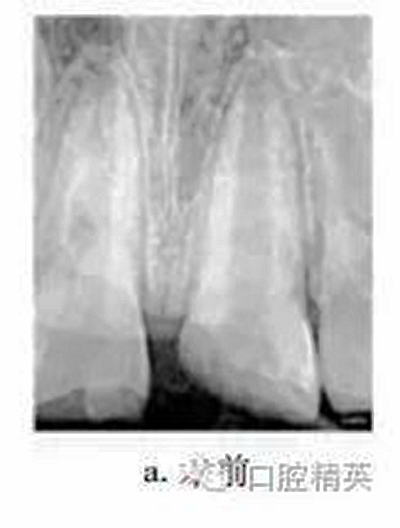

患者男,10歲。2011-06因上頜中切牙外傷就診于我院牙體牙髓病科?;颊咦允?d前患牙外傷,冷熱刺激敏感,但未行治療。檢查:11牙冠近中切角缺失,切緣釉質(zhì)缺損,無(wú)松動(dòng),探敏感,叩(+),冷熱無(wú)明顯不適;21牙冠近中斜折,邊緣銳,髓腔暴露,探診出血,探痛明顯,牙髓電活力測(cè)試(-),叩(+),無(wú)松動(dòng),牙齦未見異常,上唇腫脹。X線片示:21冠部缺損及髓,牙周膜腔增寬,根端管壁呈平行狀,根尖孔未閉合(圖a)。診斷:11釉質(zhì)缺損;21冠折。